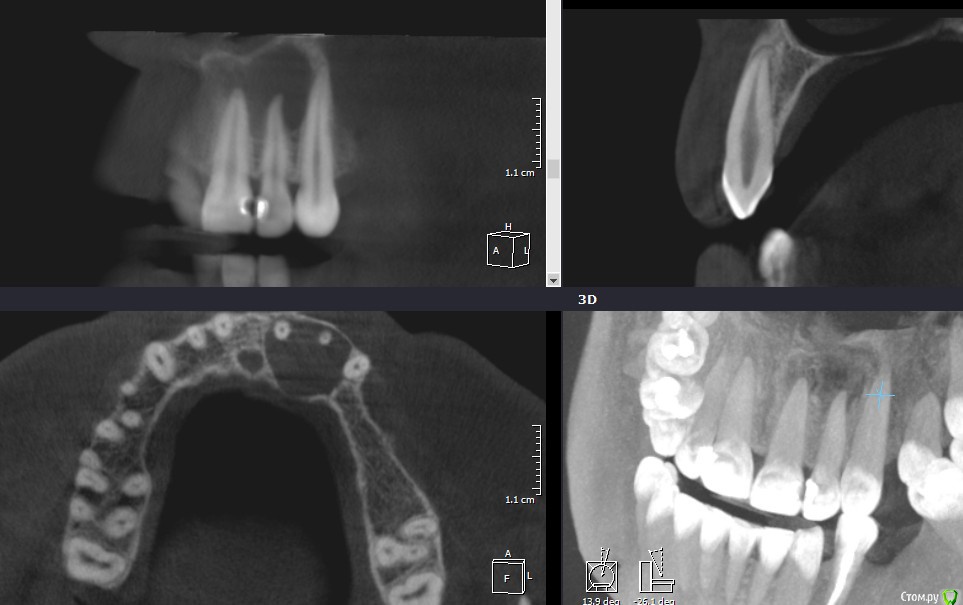

Рустам Опубликовано 17 января, 2016 Поделиться Опубликовано 17 января, 2016 Добрый вечер коллеги! Обратилась пациентка с жалобами на наличие свища в области 22 зуба. Сделали КТ, обширный очаг в области 21, 22. Как считаете, можно попытаться в данной ситуации обойтись консервативным лечением, без хирургии? Ссылка на комментарий

Л Ю С Я Опубликовано 18 января, 2016 Поделиться Опубликовано 18 января, 2016 Вот честно не вижу заочной необходимости в МТА или IRM. Первичное эндо, констрикция сохранена. И декомпрессия уже самостоятельно наладилась.Я за эндо через кальций до периода стойкой ремиссии. Далее уже закрывать, апексфикация и декомпрессия уже входе лечения по мере необходимости+1, только выясните витальность 2.1. Судя по кт он уже дохлый. Но не факт Ссылка на комментарий